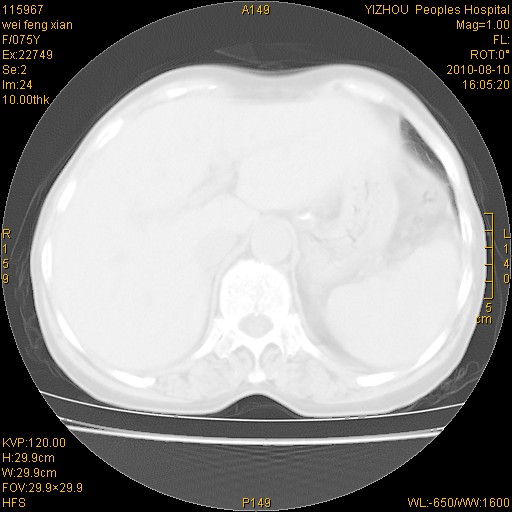

标题: CT28313:两肺弥漫性病变

女,75岁,患者反复头昏乏力面色苍白3年,再发10天入院。临床贫血查因。

考虑右肺上叶炎症合并双肺结核可能性大,建议上传纵隔窗ct图片。

结核、尘肺、支气管肺泡癌都不能除外